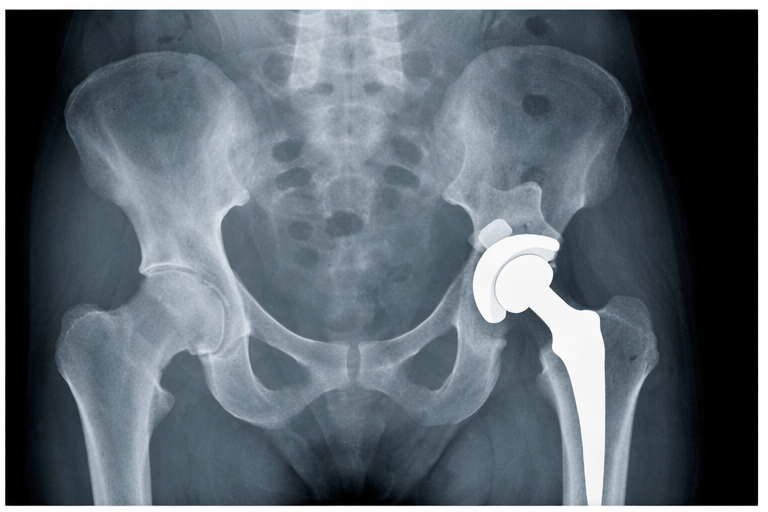

人工股関節置換術

人工股関節置換術は、股関節の変形が進行している場合に選択される手術です。傷んだ関節を人工関節に置き換えることで、痛みの改善を目指します。

人工股関節は金属やセラミックなどの素材で作られており、関節の動きを滑らかに保つ構造になっています。痛みの軽減効果が高く、術後の生活の質が改善するケースも少なくありません。

また、近年は手術技術や人工関節の耐久性も向上しており、リハビリを進めることで比較的早く歩行が可能になる場合もあります。